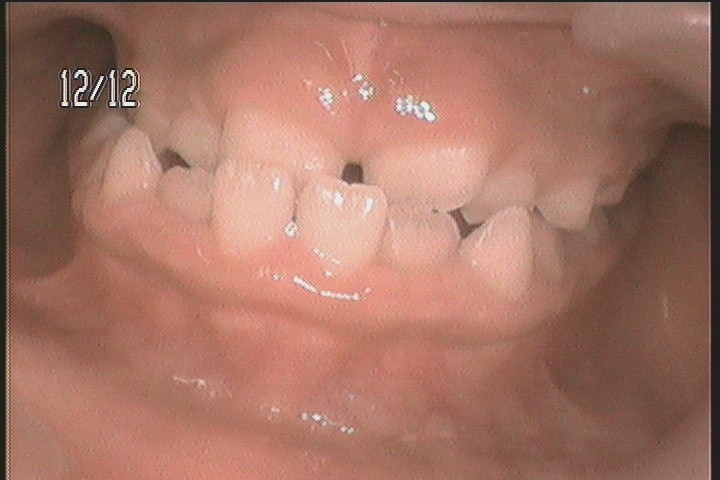

【症例05】6歳男の子|受け口が気になる

治療前

治療内容プレオルソ、筋機能療法

治療期間治療中

費用44万円(税込)※自費診療

リスク・副作用・装着中の違和感・痛み

・筋肉の疲れや軽い痛み

・長期的な継続が必要